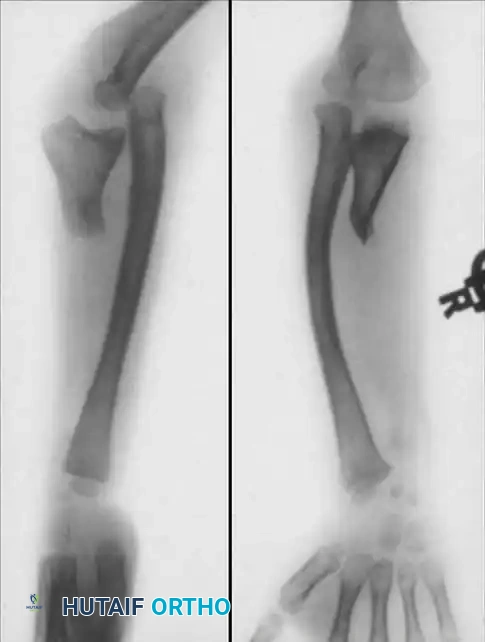

Clinical Radiograph: Preoperative anteroposterior and lateral views demonstrating congenital pseudarthrosis of the ulna with severe radial bowing and secondary dislocation of the radial head.

Surgical Radiograph: Postoperative view following excision of the radial head, creation of a synostosis between the proximal radius and ulna, and rigid fixation with an intramedullary nail.

Final Radiograph: Long-term follow-up demonstrating the final appearance and solid consolidation of the one-bone forearm.